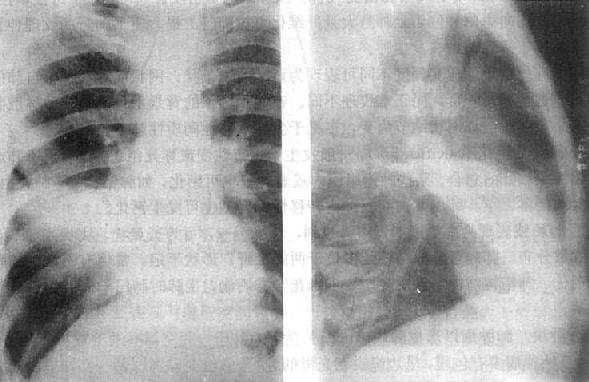

渗出性病变

图3-1-10 渗出性病变

肺浸润肺结核,两肺第1~2前肋间出现边

缘模糊、密度不太高的云絮状影

肺实变(右中叶大叶性肺炎)

图3-1-11 肺实变(右中叶大叶性肺炎)

相当于右肺中叶密度均匀增高,后前位上,上缘清楚,下缘模糊,

侧位上呈三角形致密影,尖端在肺门区